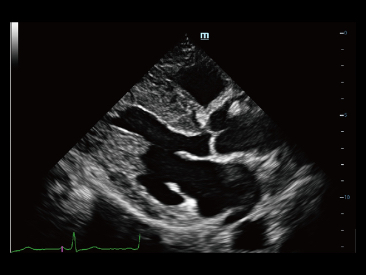

Sejak didirikan, Mindray terus mencari cara baru untuk meningkatkan keandalan diagnostik. Didukung Teknologi ZONE Sonography? terkini, platform ZST+ baru Resona 7 meningkatkan kualitas gambar ultrasound melalui pengambilan zona dan pemrosesan data saluran.

Selain kualitas gambar premium, Resona 7 juga meningkatkan kemampuan penelitian klinis dengan V Flow revolusioner untuk evaluasi hemodinamika vaskular, serta pengambilan penampang tercanggih dari rangkaian data 3D untuk diagnosis CNS pada janin. Kombinasi pengoperasian multisentuh berbasis gerakan yang paling intuitif dengan semua fitur klinis penting membuat Resona 7 menjadi gebrakan baru dalam inovasi ultrasound.